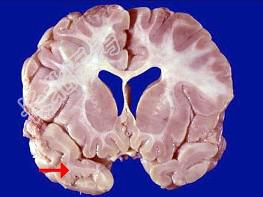

- 单项选择题如图箭头所示为大脑哪个部位 ( )

A、额叶

B、颞叶

C、枕叶

D、顶叶

E、岛叶